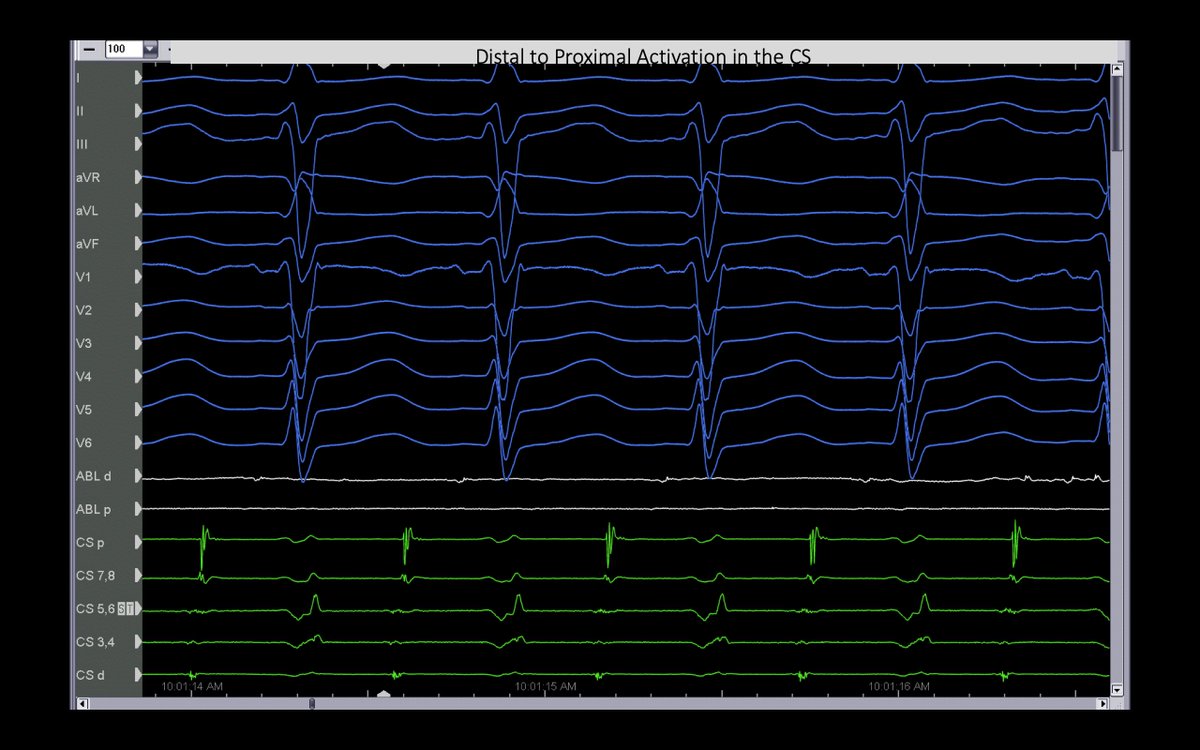

This pt with atypical AFL had a prior surgical abl at the time of MV repair. The CS d->p EGMs suggested a lateral LA source, but 3D activation had RPV carina in the circuit…which was the abl site! #mapmoreburnless @JoshSellke @maddyferraro1 @arcampado

FrischMd's tweet image. This pt with atypical AFL had a prior surgical abl at the time of MV repair. The CS d-&amp;gt;p EGMs suggested a lateral LA source, but 3D activation had RPV carina in the circuit…which was the abl site! #mapmoreburnless @JoshSellke @maddyferraro1 @arcampado